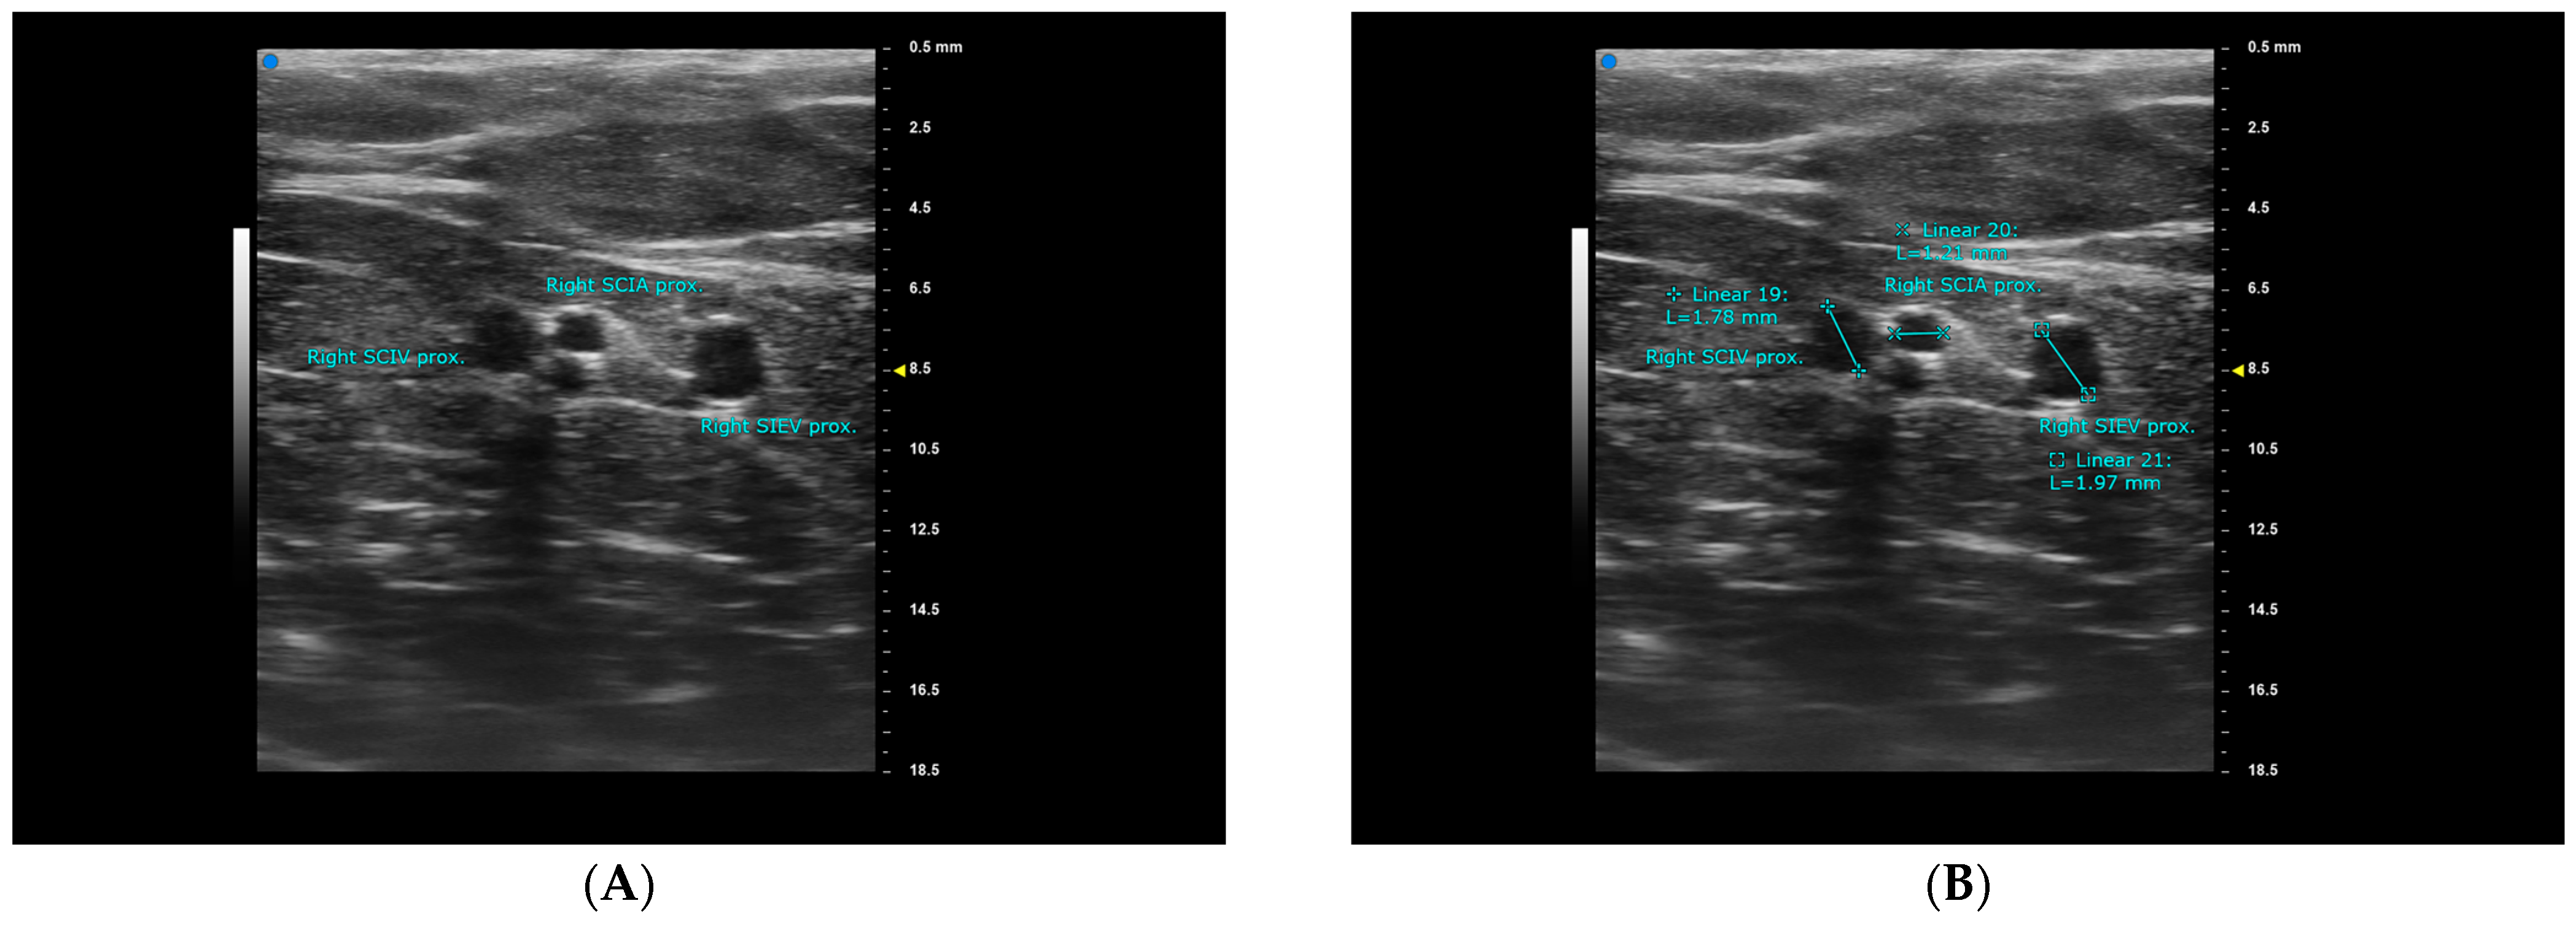

| sSCIA | SCIA VC | SCIV | |

|---|---|---|---|

| detectable at ASIS level | 48/50, 96% | 43/50, 86% | 48/50, 96% |

| Average diameter at ASIS (mean ± SD, mm) | 0.76 ± 0.25 | 0.94 ± 0.37 | 1.72 ± 0.60 |

| Average depth at ASIS (mean ± SD, mm) | 5.42 ± 2.13 | 5.42 ± 2.13 | 3.66 ± 3.29 * |

| Average diameter when traced proximal (mean ± SD, mm) | 0.97 ± 0.25 | 1.34 ± 0.58 * | 2.07 ± 0.48 * |

| Average distance to midline (mean ± SD, mm) | 91.02 ± 15.89 | 101.58 ± 17.95 | |

| Average distance to ASIS (mean ± SD, mm) | 18.71 ± 15.44 (3.27−34.15 ǂ) | 10.46 ± 14.71 * (−4.25–25.17 ǂ) | |

| Superior-lateral pedicle course | 47/48, 98% | 48/48, 100% | |

| Superior pedicle course | 1/48, 2% | 0/48, 0% | |

| Superior-medial pedicle course | 0/48, 0% | 0/48, 0% | |

| Average SCIA-SCIV distance (mm) | 15.47 ± 19.10 * |